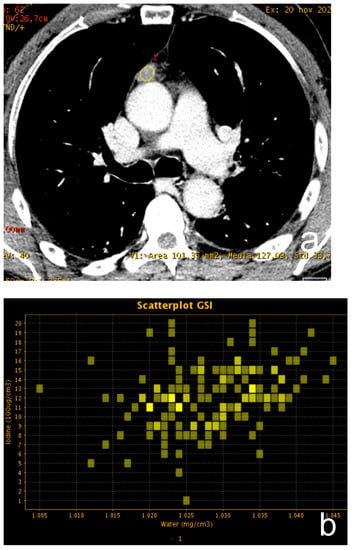

Dual-energy CT (DECT) indicates the acquisition of CT data derived from two different photon energies so that different materials can be better characterized by evaluating the difference in attenuation at these two energies [17]. Thanks to technical improvement, DECT images can be obtained with a radiation exposure not significantly different from that of a conventional single-energy CT. The scans can be performed by using different technical approaches: dual-source, single source with rapid switching, single source twin beam and dual-layer detector. Raw data can be elaborated at a dedicated workstation, thus achieving a set of monoenergetic images ranging from 40 to 140 keV and material-specific images, such as iodine and water-related. Given the increased attenuation of iodine at a low energy level, low energy series enhance lesion conspicuity with several advantages in oncologic imaging. Moreover, DECT is not affected by beam hardening artifacts, and it is possible to accurately quantify iodine uptake of tissue with better characterization of different lesions [18,19] (Figure 3).

Figure 3.

(a–c) A 62-year-old man with a small thymic lesion with convex margins. Dual-energy post-contrast images (scatterplot in (a) and spectral curve in (b) shows a mild enhancement of the lesion (mean iodine concentration 1.2 mg/dL). Histopathology revealed a medullary type A thymoma with capsule infiltration (Masaoka stage IIa).

Yen W. et al. investigated the efficacy of iodine quantification for differentiating thymoma, thymic carcinoma and thymic lymphoma. The authors enrolled 57 patients (16 low-risk thymomas, 15 high-risk thymomas, 14 thymic carcinomas and 12 lymphomas). All patients underwent dual-phase post-contrast DECT scans in arterial and venous phases, and the following parameters were analyzed: iodine-related Hounsfield Unit (IHU), iodine concentration (IC), mixed HU (MHU), slope HU curve and virtual non contrast (VNC) values. The results demonstrated that IHU, IC and MHU were significantly higher in patients with low-risk than high-risk thymoma, thymic carcinoma and lymphoma: IHU in the venous phase showed the best performance for differentiating low-risk thymomas from the other tumors, with an AUC of 0.893 and a cut-off of 34.3 HU, while IC in the venous phase performed well for differentiating low-risk thymoma from lymphoma, with an AUC of 0.969 and a cut-off of 1.25 mg/mL. The higher values of DECT parameters in low-risk thymomas can be explained by the high prevalence of short-spindled variant among types A and AB thymomas, which are composed by short spindle cells arranged in a hemangiopericytic structure with a rich vascularization [20].

Xie Y. et al. [21] investigated the possibility of DECT to distinguish thymoma from mediastinal lymphoma because there is a significant overlap between the two diseases on conventional single-energy contrast CT. A total of 39 patients (24 with thymoma and 15 with lymphoma) were enrolled. DECT scans of the thorax were performed both in post-contrast arterial and venous phases by using fast tube voltage switching between 80 and 140 kVp. The following parameters were assessed for each lesion: normalized IC (NIC), calculated as the ratio between IC of the lesion and aorta, slope of spectral curve between 40 and 140 keV and CT attenuation difference, which is the difference in attenuation between arterial and venous phase at 70 keV. Data analysis showed a significant difference in NIC between patients with thymoma and lymphoma in venous phase (0.49 ± 0.15 mg/mL vs. 0.28 ± 0.08 mg/mL, respectively) and a significant higher slope of the spectrum curve in patients with thymoma in arterial phase. The higher IC of thymoma in the venous phase can be explained by the coexistence of neoplastic cells and fibrous bands within thymic lobules, which delay the washout of contrast medium. On the contrary, lymphomatous tissue lacks fibrous septa, and therefore the lesion washes out quickly after arterial phase.